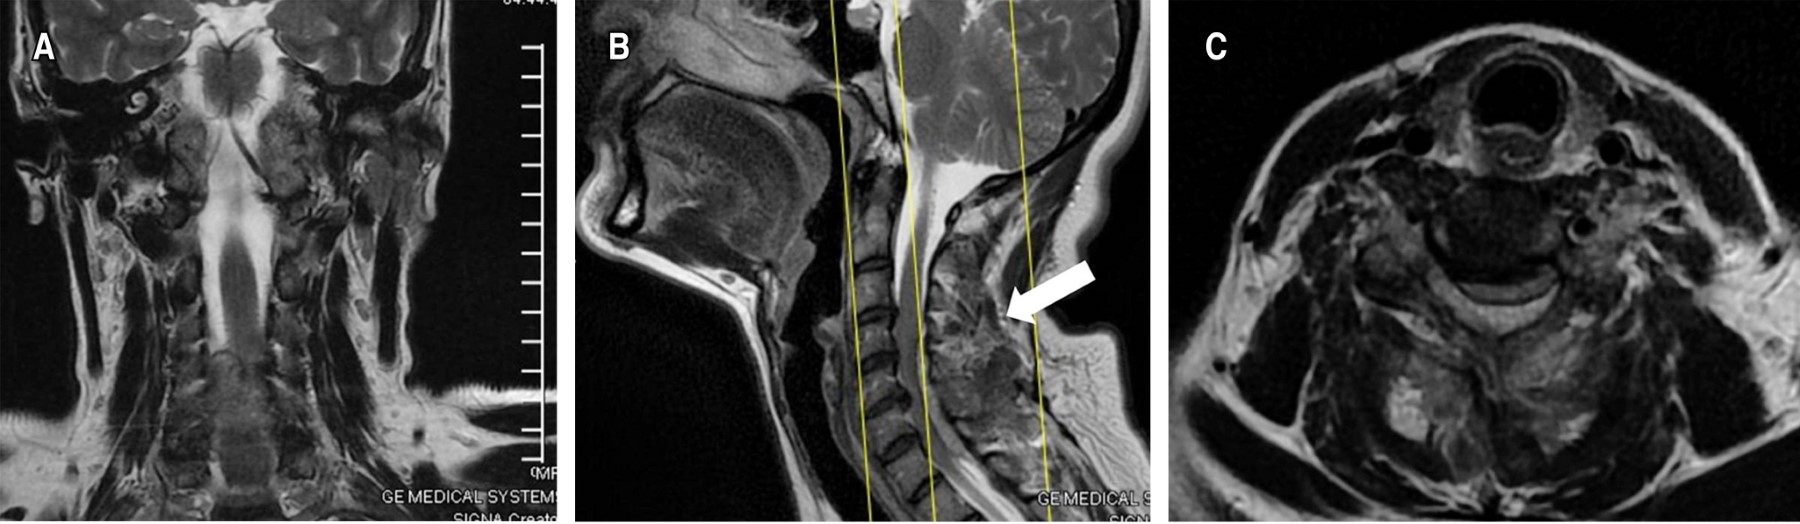

Ewing sarcoma (ES) is a malignant tumor that generally occurs in pediatric males. Its location in the neck is rare, with extraosseous presentation in this area being exceptional (3.4%), even more if it is extramedullary intradural. The presence of non-specific clinical symptoms makes early detection difficult, which tends to occur when the tumor causes spinal cord involvement, requiring an urgent surgical approach. We present the case of a 49-year-old female patient with neck pain of two years' duration, who after a symptomatic exacerbation lasting one month, presented right hemiparesis and loss of sphincter control. Diagnostic approach with magnetic resonance imaging showed multidirectional bulging of the annulus fibrosus measuring 300 × 300 × 100 mm, located at C3-T1 that compressed the dural sac plus bilateral neural foraminal involvement. Surgical management through a posterior cervical approach plus stabilization of lateral masses from C3 to C7, with a histopathological report of Ewing sarcoma complemented by detection of the t(11;22)(q24;q12) translocation of EWSR1. After surgery, the patient showed improvement with independence in work activity and daily life.

Figure 2